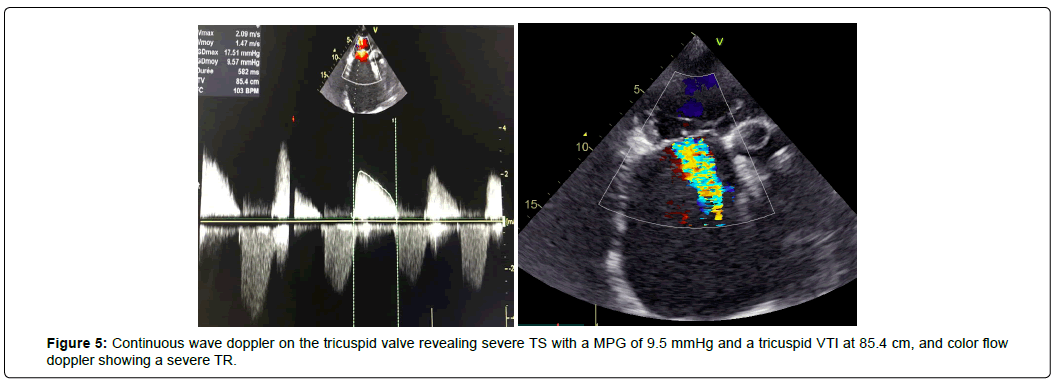

We also found a severe Tricuspid Stenosis (TS) with a MPG of 9.5 mmHg and a tricuspid veloctiy time integral (VTI) of 85.4 cm and a severe organic Tricuspid Regurgitation (TR) (Figure 5), and restricted mobility of pulmonary cusps with moderate PS with a MPG of 43 mmHg (Figure 6) and mild Pulmonary Regurgitation (PR). The patient had bi-atrial enlargement and a very dilated inferior vena cava (figure 7). Biventricular function was normal, with a Left Ventricular Ejection Fraction (LVEF) of 55% and a Global Longitudinal Strain (GLS) of -19.5% (figure 8). LV dimension during systole (LVDs = 24cm/m2) and diastole (LVDd = 30cm/m2) were normal, Interventricular Septal Thickness (IVST) and Posterior Wall Thickness (PWT) were also normal (10 and 9 mm respectively). Pulmonary artery pressure couldn’t be assessed using conventional echocardiographic methods.